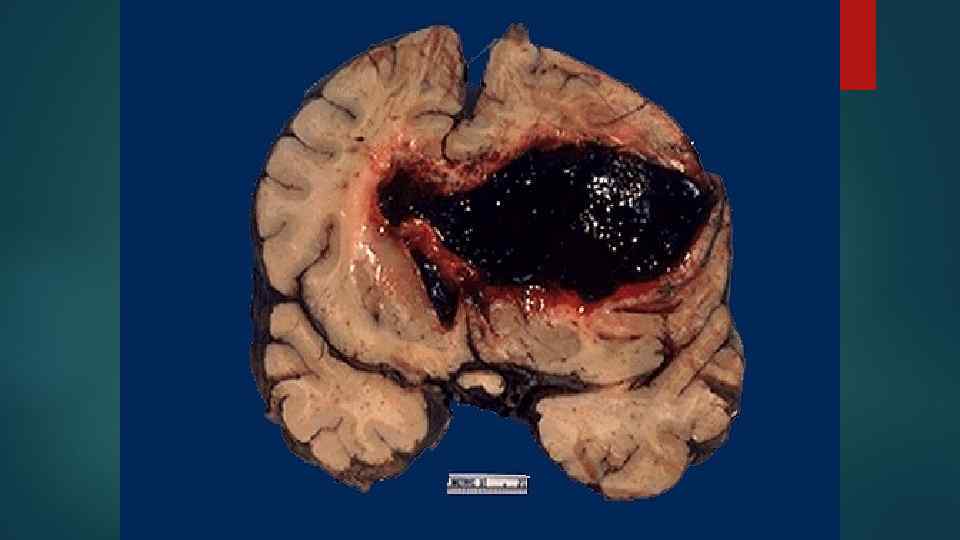

Причины смерти при ОЛ 1. Кровоизлияния в жизненно важные органы 2. Осложнения, связанные с некротически-язвенными процессами 3. Присоединение инфекции 4. Угнетение функции КМ 5. Осложнения терапии